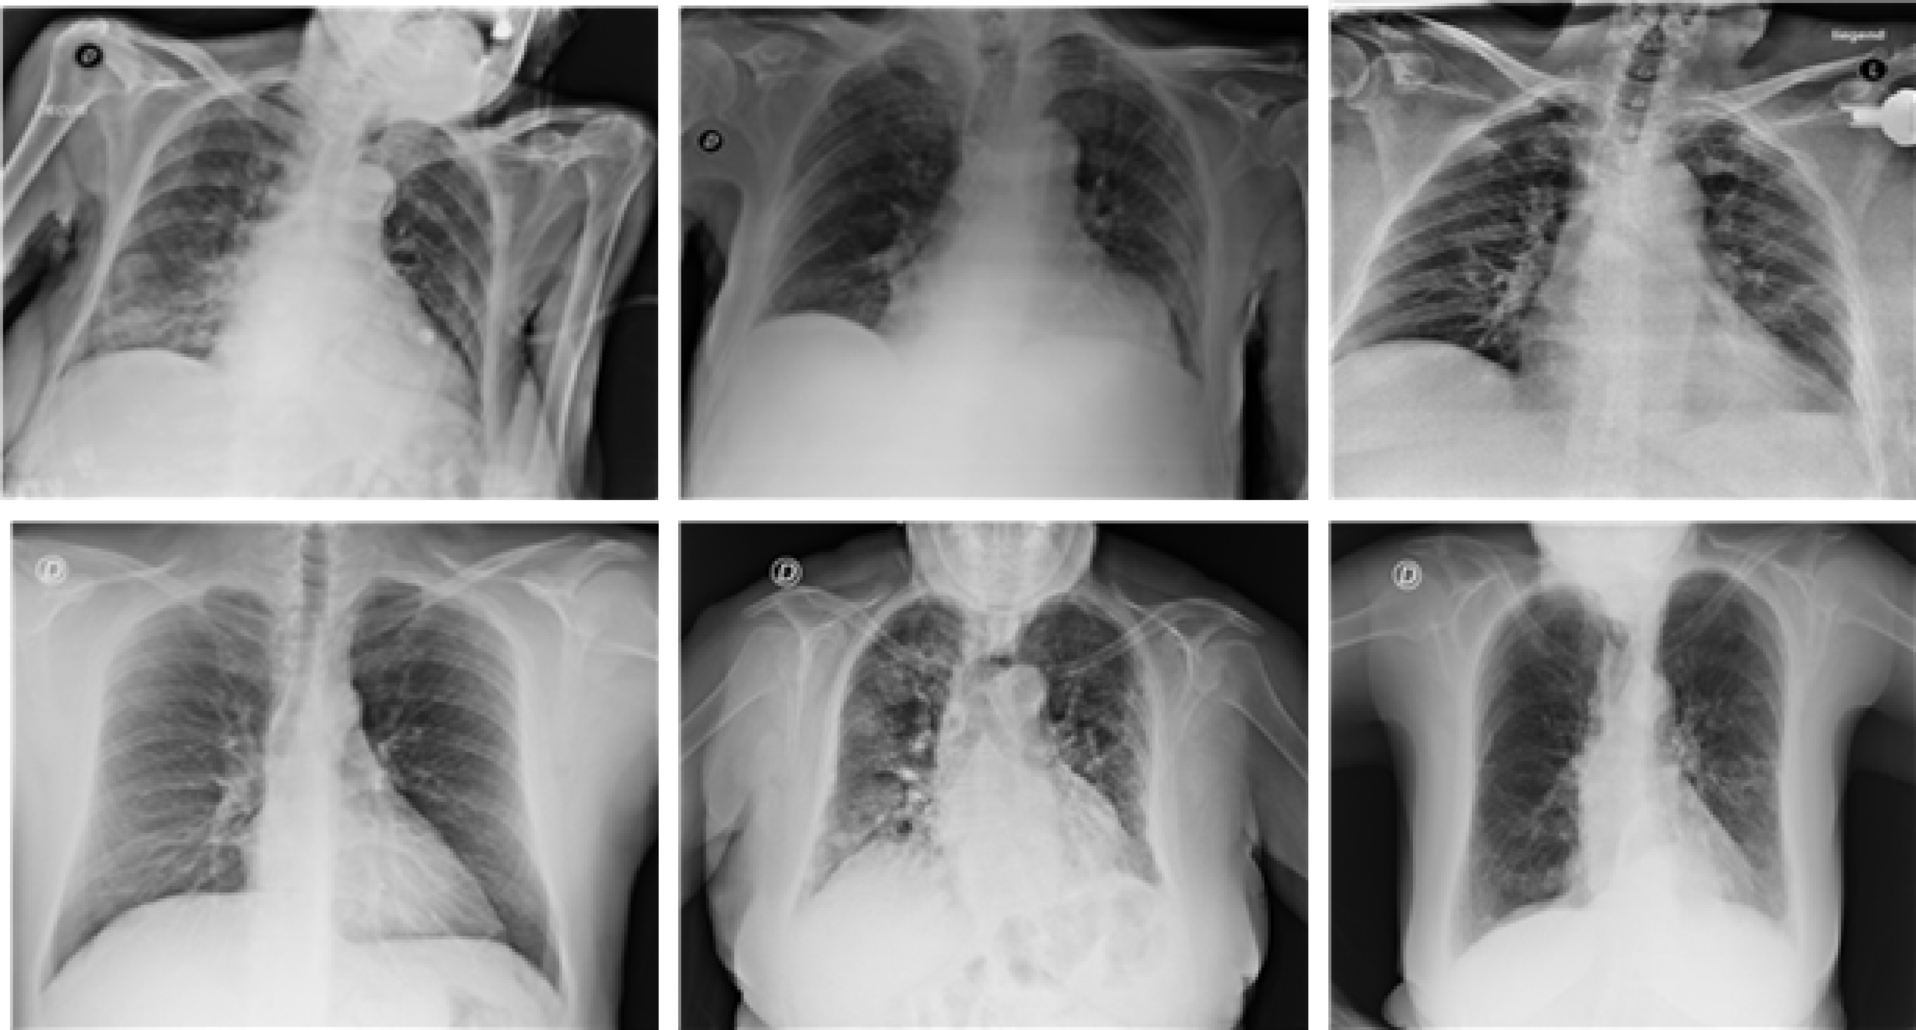

Fig. 3

Visualization of sample images COVID-19 Chest X-ray image dataset (https://www.kaggle.com/datasets/prashant268/chest-xray-covid19-pneumonia).